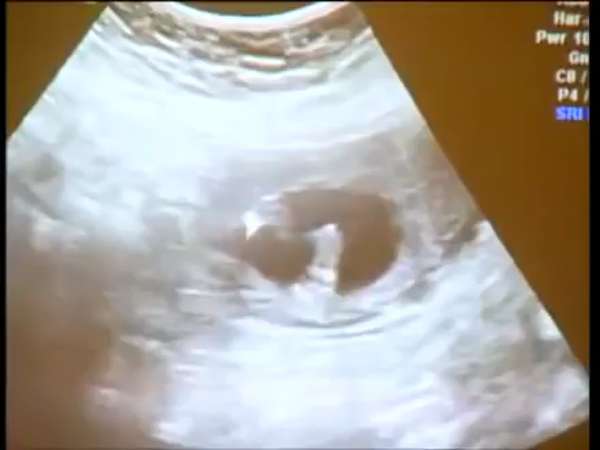

13 Haftalık Gebelik

402 izlenme